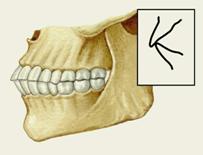

Рис. 7а). Схематическое изображение челюстей при открытом прикусе. |

Рис. 7б). Схематическое изображение челюстей при глубоком прикусе.

Рис. 7в). Схематическое изображение челюстей при перекрестном прикусе.